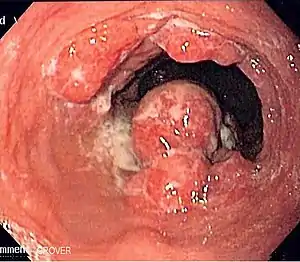

Endoscopic image of an esophageal adenocarcinoma